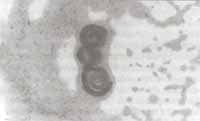

También se practicó intubación orotraqueal y ventilación mecánica, soporte inotrópico y transfusión de glóbulos rojos. Se realizó fibrobroncoscopia diagnóstica con lavado broncoalveolar, confirmándose la presencia de abundantes larvas de Strongyloides stercoralis (Figura No. 5).

Figura No 5. Lavado broncoalveolar: Fondo hemorrágico en medio del cual se observan larvas de Estrongiloides. Coloración Diff-Quick 10x.